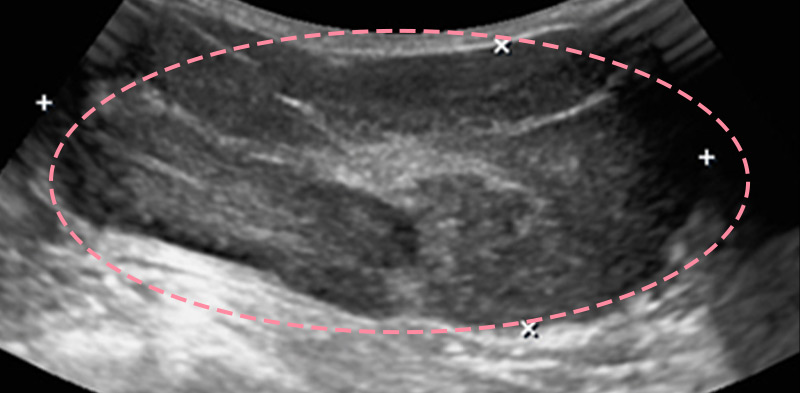

유방 양성 종양은 한 개만 나타나는 것이 아니라 동시다발적으로 생겨나기도 합니다.

여러 개의 양성 종양 제거는 정상적인 유방 조직을 온전히 보전할 수 있도록 섬세한 시술이 필요합니다.

한송이 원장은 다발성 종양 제거에 대한 풍부한 경험을 토대로, 무리 없이 맘모톰 조직검사 및 제거를 진행했습니다.

맘모톰시술 6개월 후 유방초음파 검사 시행 결과 종양이 깨끗하게 제거됨을 확인했으며, 약간의 반흔 조직이 남았으나 시간이 지나면서 대부분 사라지기 때문에 좋은 예후가 기대되었습니다.